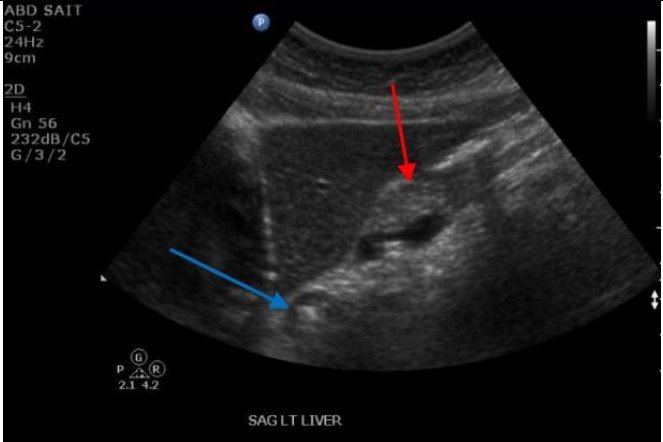

Label the Red and blue arrows

Red: Body of pancreas

Blue: GE junction